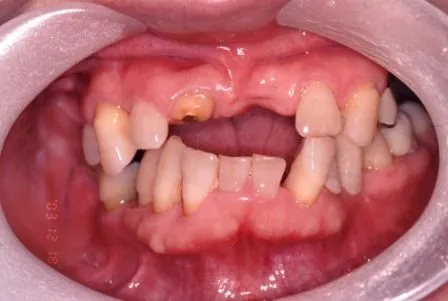

症例3

上顎右上2、左上13に抜歯と同時にインプラントし、セラミックメタルボンドブリッジ